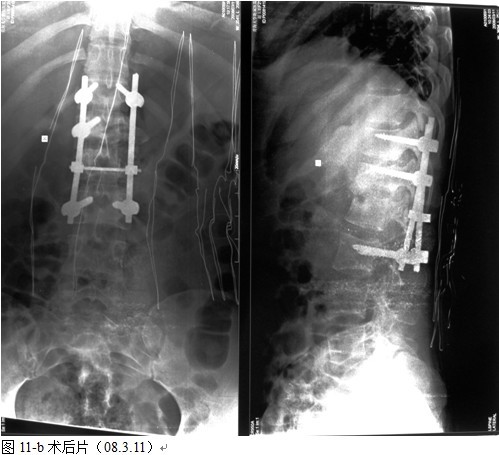

图11-a术前

以病变椎体为中心,作一后正中切口,显露病椎棘突、椎板、关节突以及上下需要固定的正常椎体,根据后凸畸形的严重程度在C 型臂协助下确定进钉角度和方向,置入椎弓根钉,椎弓根钉固定的方法:病灶上下相邻正常椎体置入,当病椎骨质破坏不超过1/3或未累计椎弓根时置入相对较短的钉子,一般长度为35mm,当骶1椎体有破坏时,根据骨质的情况确定入钉的方向,将病椎上、下关节突关节切除,自椎间孔显露病灶,直视神经根状态下进行病灶清除和椎管减压,可将干酪样物,死骨,坏死的椎间盘大部分清除,解除硬膜囊的压迫,必要者可双侧同时病灶清除,减压。无钛棒状态下用椎体撑开器轻柔牵开,采用前路撑开结合后路固定维持有限撑开或加压缓慢矫正脊柱后凸畸形,特别注意是由于结核患者骨质疏松,不可用钉棒大力撑开,否则钉子拔出可能性较大。要前路撑开加后路加压来达到矫形的目的。撑开后,缺损空间增大,大部分用手指可触及缺损内的情况,能进一步彻底清除病灶及对侧的病灶,反复用异烟肼盐水混合液冲洗病灶,凿出植骨床,植骨时需注意植骨块要采用“平进竖植”方法,循序用植骨打入器和辅助器械缓慢植入否则易导致神经根损害。植骨完成后再次采用内固定适当加压促使骨块稳定及融合,如果病灶中的脓液稀薄较多时,在病灶中留置一根硬膜外管,术后注射异烟肼,每周两次,以提高局部的药物浓度,在对侧椎板,关节突间植骨,病灶内留置链霉素2.0g ,放置引流管,闭合伤口。